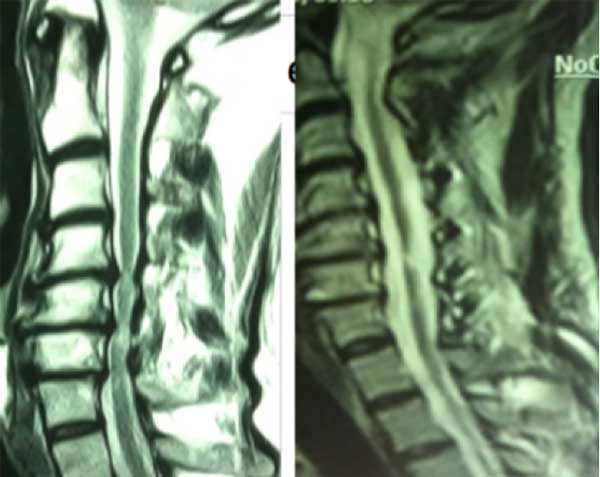

Paciente masculino de 73 años, con tetraparesia progresiva a predominio de miembros superiores e hipoestesia marcada en ambas manos de dos meses de evolución con escasa respuesta al tratamiento médico. Al examen físico: debilidad en 4 miembros a predominio distal en miembros superiores, alteración en la motricidad fina, aumento de base de sustentación. Refería episodios de incontinencia vesical. Nurick prequirúrgico de 4. En RM se observan protrusiones discales múltiples con estrechamiento del canal cervical y compresión de cara anterior medular (Figura 7). Se propuso realizar una laminoplastia entre los niveles C3-C7. Nurick postquirúrgico de 3.

Figura 7. Comparativa de corte sagital de RM T2 cervical prequirúrgica (izquierda) donde se observan múltiples protrusiones discales y estrechamiento del canal espinal cervical con compresión anterior medular predominantemente en los segmentos C4-C6. La imagen derecha muestra el control posquirúrgico con una notoria ampliación del canal espinal y disminución de la compresión anterior de la médula.